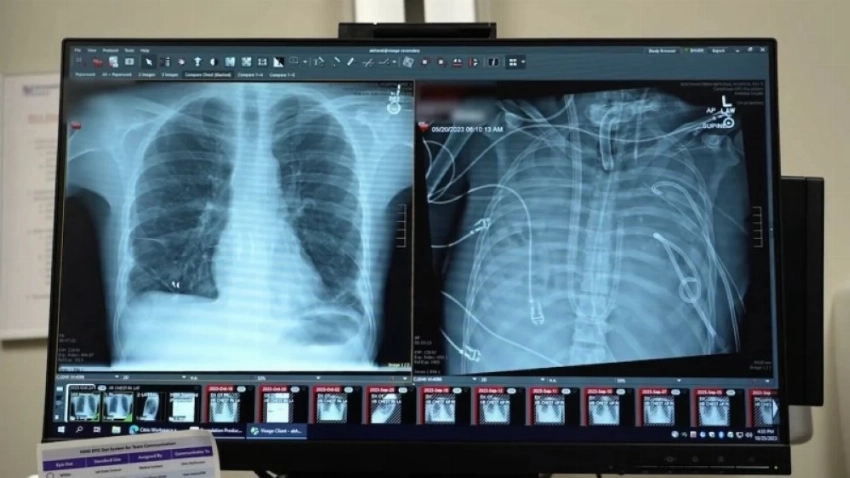

في إنجاز طبي غير مسبوق، تمكّن أطباء وجراحون في مستشفى نورث وسترن ميديسن بمدينة شيكاغو من إبقاء مريض في حالة حرجة على قيد الحياة لمدة 48 ساعة بعد إزالة رئتيه بالكامل، وفق ما أعلن المستشفى.

وكان المريض، بحسب شبكة «فوكس نيوز» وهو رجل يبلغ من العمر 33 عاماً من ولاية ميزوري، قد نُقل جواً إلى مستشفى نورث وسترن التذكاري في ربيع عام 2023 بعد إصابته بفشل رئوي حاد ناتج عن عدوى إنفلونزا، ومع تدهور حالته، تطورت الإصابة إلى التهاب رئوي شديد وتعفن دم (إنتان)، ما أدى إلى توقف قلبه واضطرار الفريق الطبي إلى إجراء الإنعاش القلبي الرئوي.

ولمواجهة هذا التحدي، صمّم الفريق الطبي نظاماً مبتكراً أُطلق عليه اسم «نظام الرئة الاصطناعية الكاملة» (TAL)، تولّى وظائف تبادل الغازات (تزويد الجسم بالأكسجين والتخلص من ثاني أكسيد الكربون)، إلى جانب الحفاظ على تدفق الدم الطبيعي إلى القلب، بينما ظل المريض على أجهزة دعم الحياة.

وبعد مرور 48 ساعة، استقرت حالة المريض بما يكفي لإجراء زراعة رئتين مزدوجة ناجحة. وبعد مرور نحو عامين على العملية، عاد المريض إلى حياته الطبيعية.